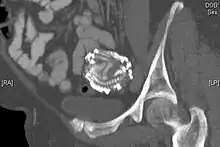

An 80-year-old woman presented in the outpatient department with severe abdominal pain. Ultrasound examination revealed a large echogenic mass (20 x 20 cm) in the right upper quadrant. An abdominal x-ray demonstrated the skeleton of a fully developed extrauterine fetus. It is presumed from the patient's history that this fetus was present for at least 40 years. Radiography revealed a fetus shrouded in a mantle of calcification. The fetus was hyper-flexed with other signs of "intrauterine" death. Fetal dentition charts dated the fetus at 34 weeks, the epiphyses being obscured by extensive calcification. In addition to subcutaneous calcification there was extensive visceral and intracranial calcification.[24] |